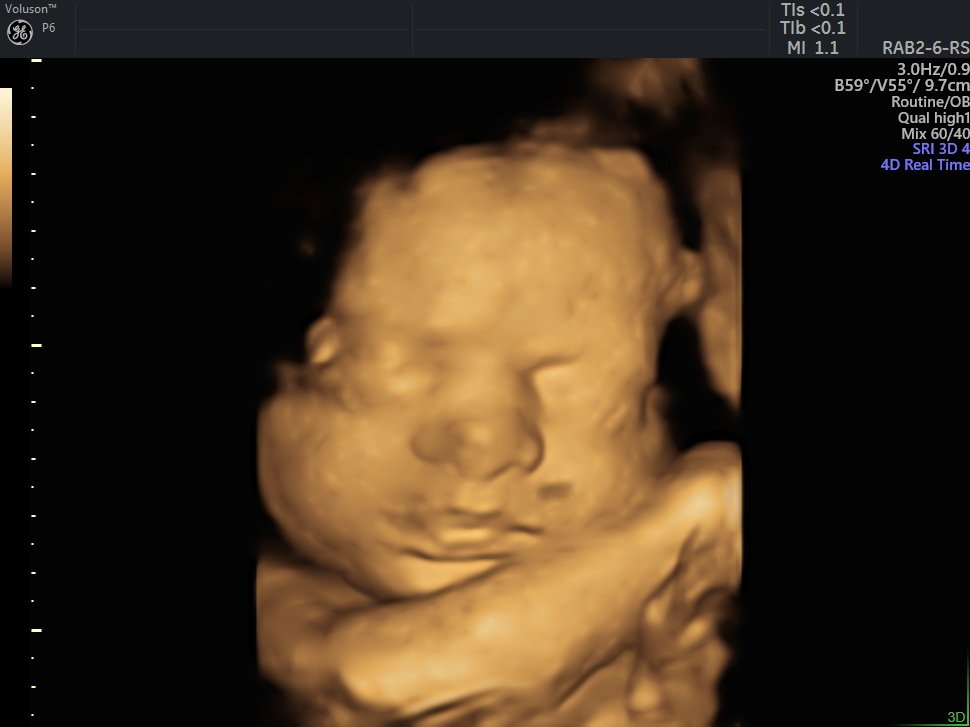

4 D Ultrasonografi

4 Boyutlu (Renkli) Ultrason ve Doppler Ultrasonografi